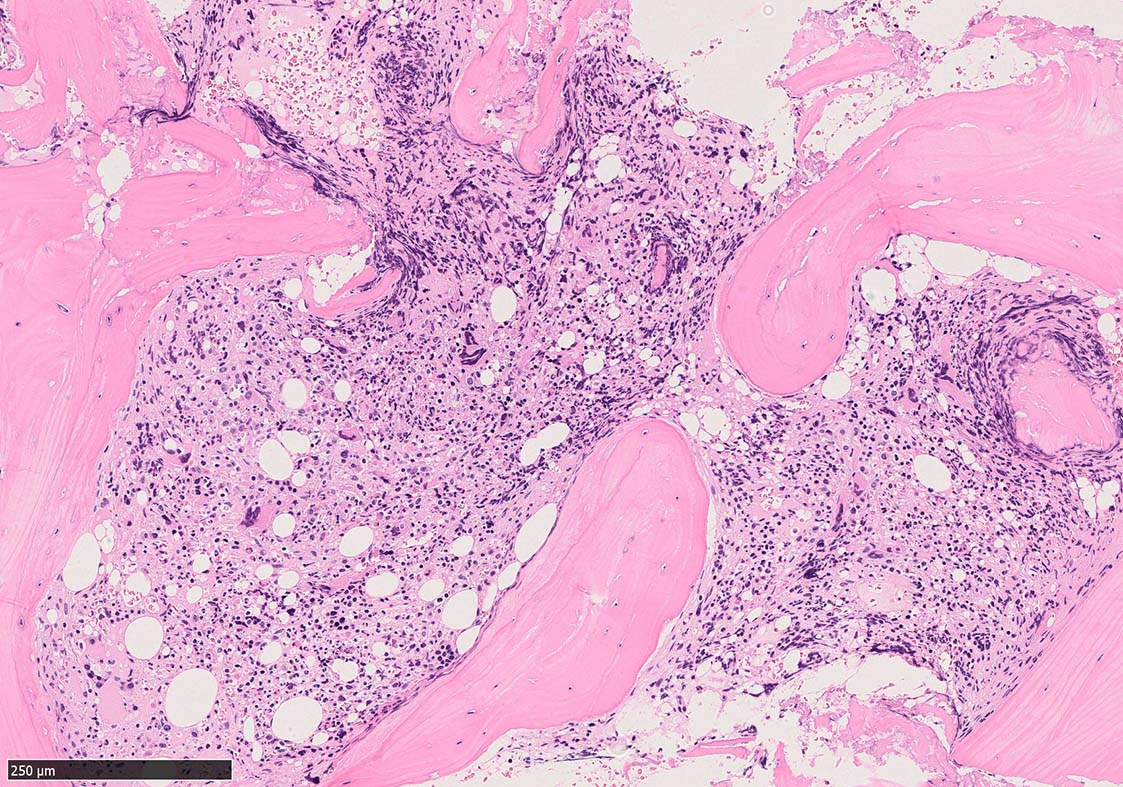

骨髄組織所見 bone marrow biopsy total 6mm in length

Case02; Meylofibrosis, overt fibrosis

黒染する弾性線維の増生のほか, 赤く染まる膠原線維の増生が確認される. MF-2 fibrosis. 鍍銀染色の核染色をすると膠原線維の赤染がわからなくなるので行わない.